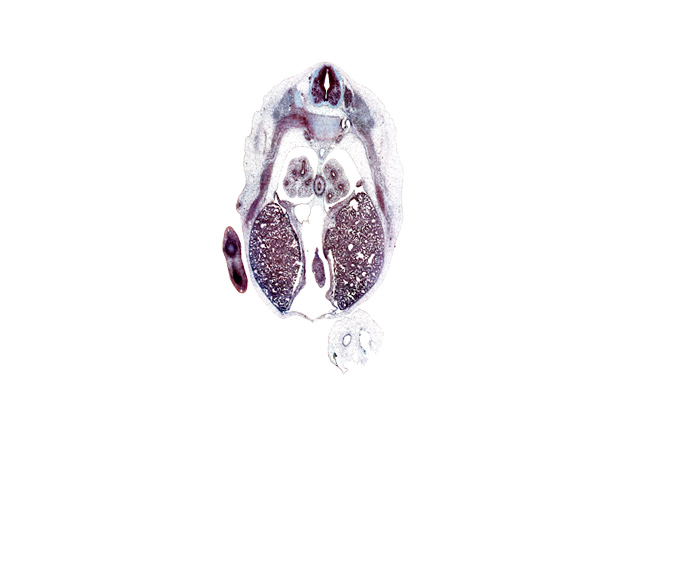

Carnegie Embryo #9325 | Location: 20-3-3

Keywords: T-6 intercostal nerve, T-6 spinal ganglion, T-6 spinal nerve, caudal edge of left ventricle, central tendon of diaphragm, hand plate, iliocostalis muscle, inferior vena cava, left lobe of liver, longissimus muscle, lower lobe of right lung, mammary gland, neural arch, pericardial cavity, peritoneal cavity, pleural cavity, pleuropericardial membrane, pleuroperitoneal foramen, rib 7, right lobe of liver, spinalis muscle, subarachnoid space, sympathetic trunk

Source: The Virtual Human Embryo.